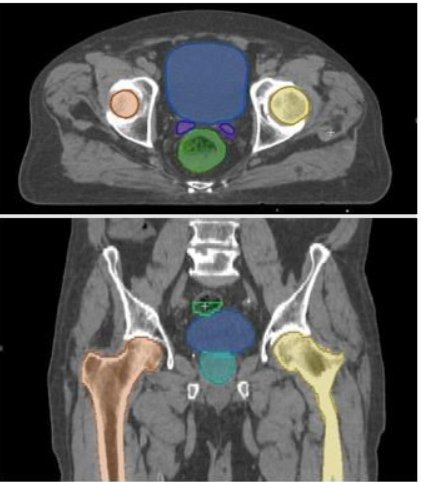

Segmentation is the identification of anatomic structures and pathology within medical images. It serves as the essential first step in numerous clinical applications, including diagnosis, treatment planning, quantitative analysis of imaging for research, and radiotherapy planning. Image segmentation has historically been a manual, time-intensive workflow requiring significant expertise, which has hindered the adoption of many promising advanced technologies. In recent years the advent of Artificial Intelligence (AI) segmentation has become faster and more efficient enabling the broader use of personalized and precision medical technologies.

While segmentation is central to a wide array of applications, the type of output it produces must often be customized for its intended use. As an example of this challenge, consider preoperative planning, a process where surgeons use digital tools (including 3D models and imaging data), to visualize anatomy, assess potential risks, and make critical decisions about a procedure before it is performed. Planning applications rely on tessellated 3D models (often stored as STL files created from segmentation data) for simulation, visualization, and analysis. These models are ideal for creating 3D printed patient-specific instrumentation and for robotic assisted intervention, but cannot be used directly for developing or adapting the AI models used for segmentation. AI model training requires a different type of output called an "image mask" which encodes segmentation data as a binary representation where each pixel is classified as part of a structure of interest or not.